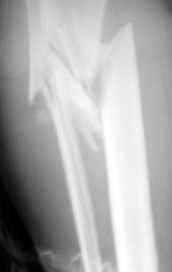

Больная поступила 11 12 2004 с открытым оскольчатым переломом в/3 обеих костей правой голени со смещением после автодорожной аварии. (1Б по Каплану, тип 2-классификация Gustilo-Anderson).

Наложено скелетное вытяжение . обработана рана, наложены швы, заживление идет благоприятно. На контрольных рентгенограммах стояние отломков несколько улучшилось. Рис 1,2 Обдумываем в коллективе несколько вариантов возможного лечения:

На снимке не видно, как далеко по диафизу идет линия перелома. На мой взгляд, лучше сделать еще один снимок, как бы не пришлось делать АВФ из 4

опор.

Рентгенограмма при поступлении. Думаю на ней видно распространение линии перелома вниз